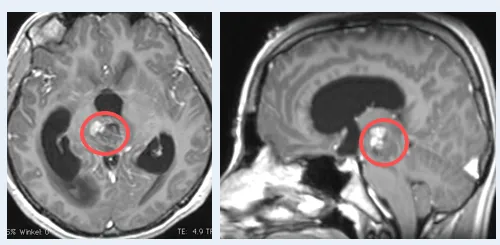

在神经外科领域,脑干海绵状血管瘤被视为一颗不定时炸弹。36岁的Jack便是一位与这种疾病抗争三年的患者。 更特殊的是,他的病灶分布在基底节、小脑及中脑多个关键区域,医学上称为多发...